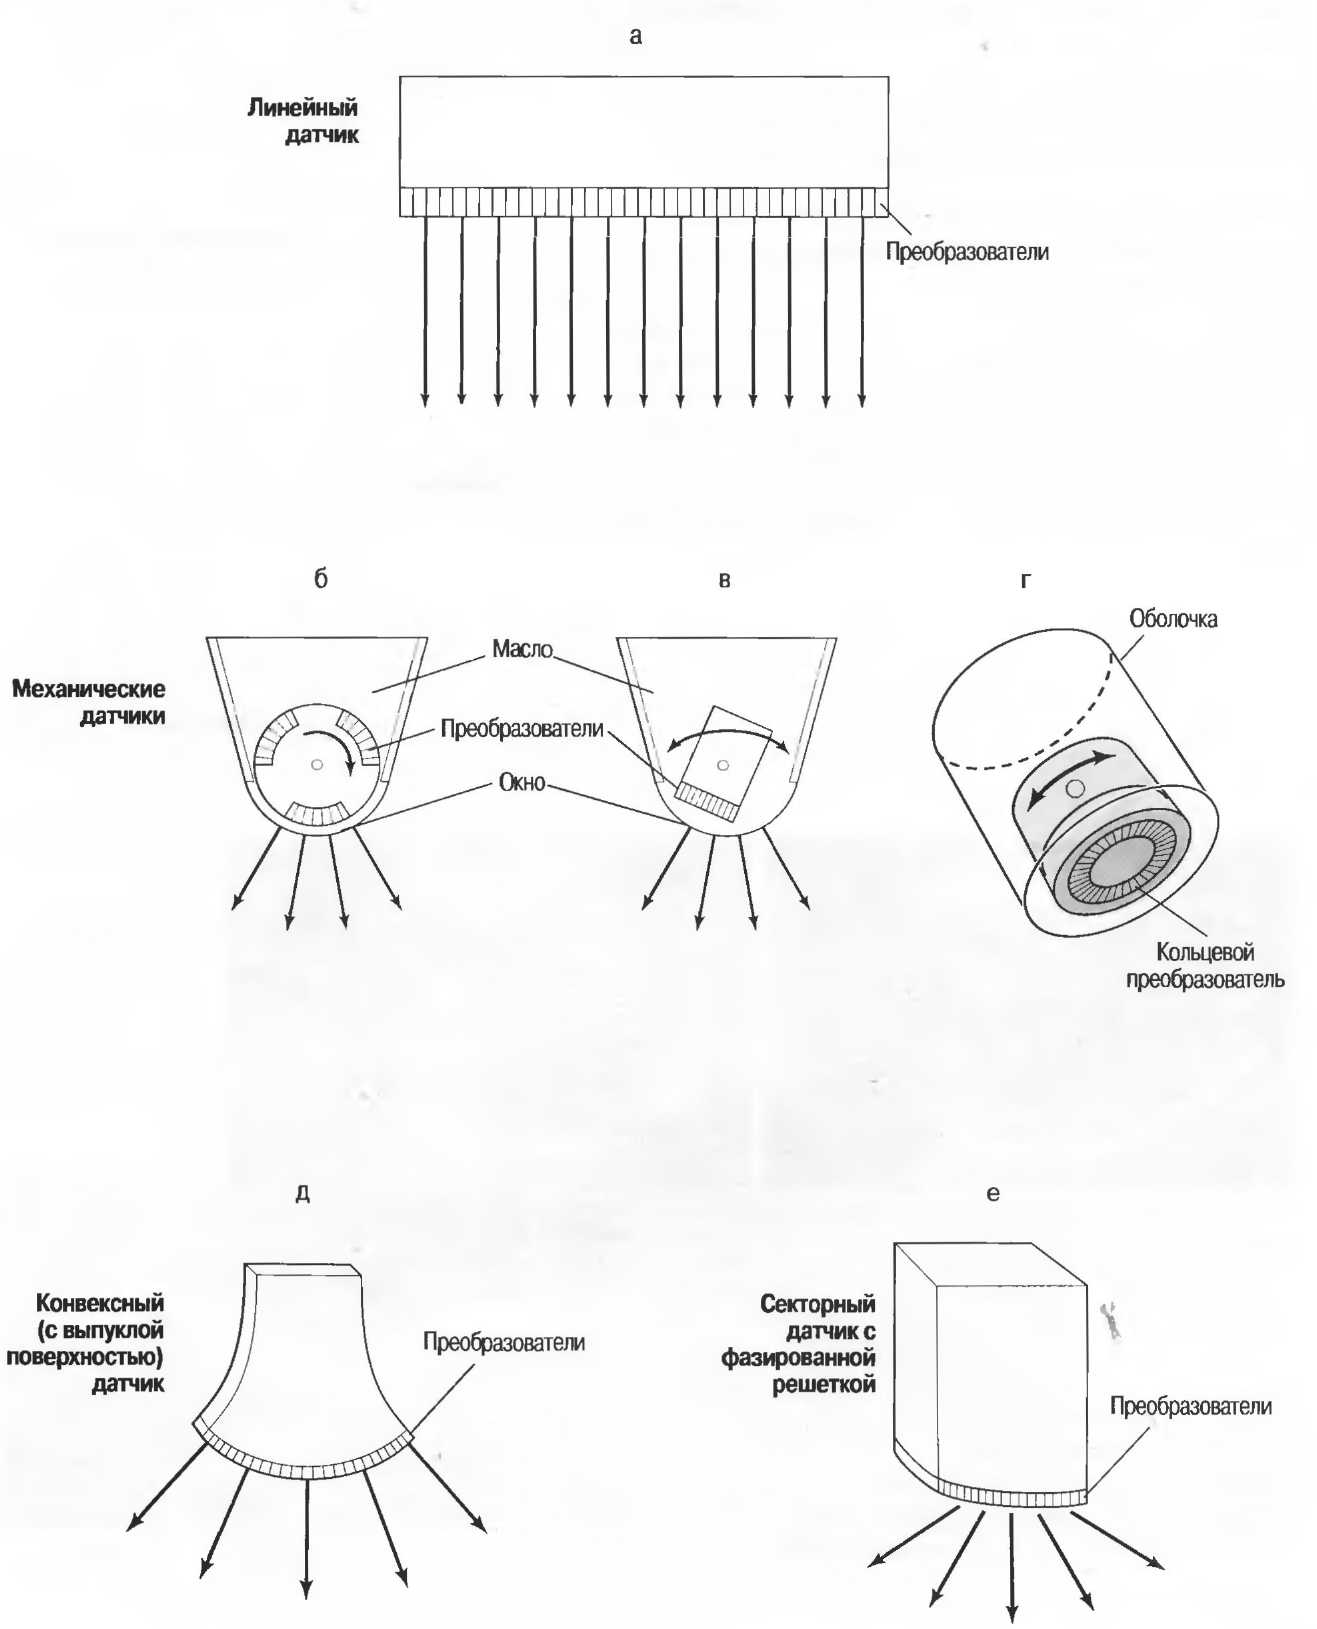

Форма среза, получаемая при использовании различных датчиков

1. Линейный датчик. Срезы при использовании таких датчиков имеют форму прямоугольников. Эти датчики наиболее удобны в акушерских исследованиях, а также при исследовании щитовидной и молочных желез (рис. 7а).

Рис.7а. Срезы прямоугольной формы, получаемые при использовании линейного датчика.

2. Секторный датчик. Срезы имеют форму веера, почти треугольного. Эти датчики удобно использовать при наличии очень небольшого по площади, доступного для исследования пространства. Они используются для исследования верхних отделов брюшной полости, а также в гинекологии и кардиологии (рис. 76).

Рис.7б. Срезы в форме веера, получаемые при использовании секторного датчика.

3. Конвексный датчик. Получаемый срез имеет форму, промежуточную между формой среза линейного и секторного датчиков, и используется для сканирования всех частей тела, кроме эхокардиографии (рис. 7в).

Рис.7в. Широкополосный веерообразный срез с широкой, изогнутой вершиной отконвексного датчика.